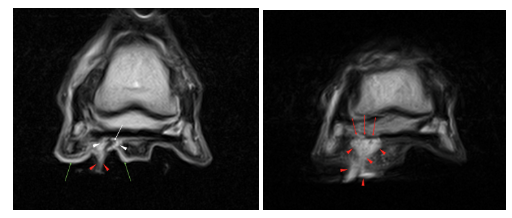

As expected, STIR and T2 FSE images revealed a hypointense pocket in the solar dermis (white arrow) surrounded by a halo of signal hyperintensity (white arrowheads) indicating the region of subsolar haemorrhage and infection. The location of this pocket and halo, the focal point of infection, was shown to be within the soft tissue at the plantar border of the most distal aspect of the deep digital flexor tendon. The signal intensity within the tendon fortunately appeared normal.

On the same images, draining material was shown to be exiting close to the lateral sulcus of the frog (red arrowheads). The solar dermis was diffusely hyperintense and thick (green arrows), again consistent with diffuse inflammation and subsolar infection.